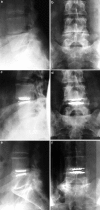

A retrospective clinical-radiological study to evaluate the long-term outcome after artificial disc replacement was performed. The objective is to investigate long-term results after implantation of a modular type artificial disc prosthesis in patients with degenerative disc disease (DDD). Total disc replacement (TDR) is a surgical procedure intended to save segmental spinal function, and thus replace spondylodesis. Short-term results are promising, whereas long-term results are scarce. The Charité TDR is the oldest existing implant, therefore, the longest possible follow-up is presented here. Seventy-one patients were treated with 84 Charité TDRs types I-III. Indication for TDR was moderate to severe DDD. Fifty-three patients (63 TDRs) were available for long-term follow-up of 17 years. Evaluation included Oswestry disability index, visual analog scale, overall outcome score, plain and extension/flexion radiographs. Implantation of Charité TDR resulted in a 60% rate of spontaneous ankylosis after 17 years. No significant difference between the three types of prostheses was found concerning clinical outcome. Reoperation was necessary in 11% of patients. Although no adjacent segment degeneration was observed in the functional implants (17%), these patients were significantly less satisfied than those with spontaneous ankylosis. TDR, nowadays, is an approved procedure. Proof that long-term results of TDR implantation in DDD are at least as good as fusion results is still missing.